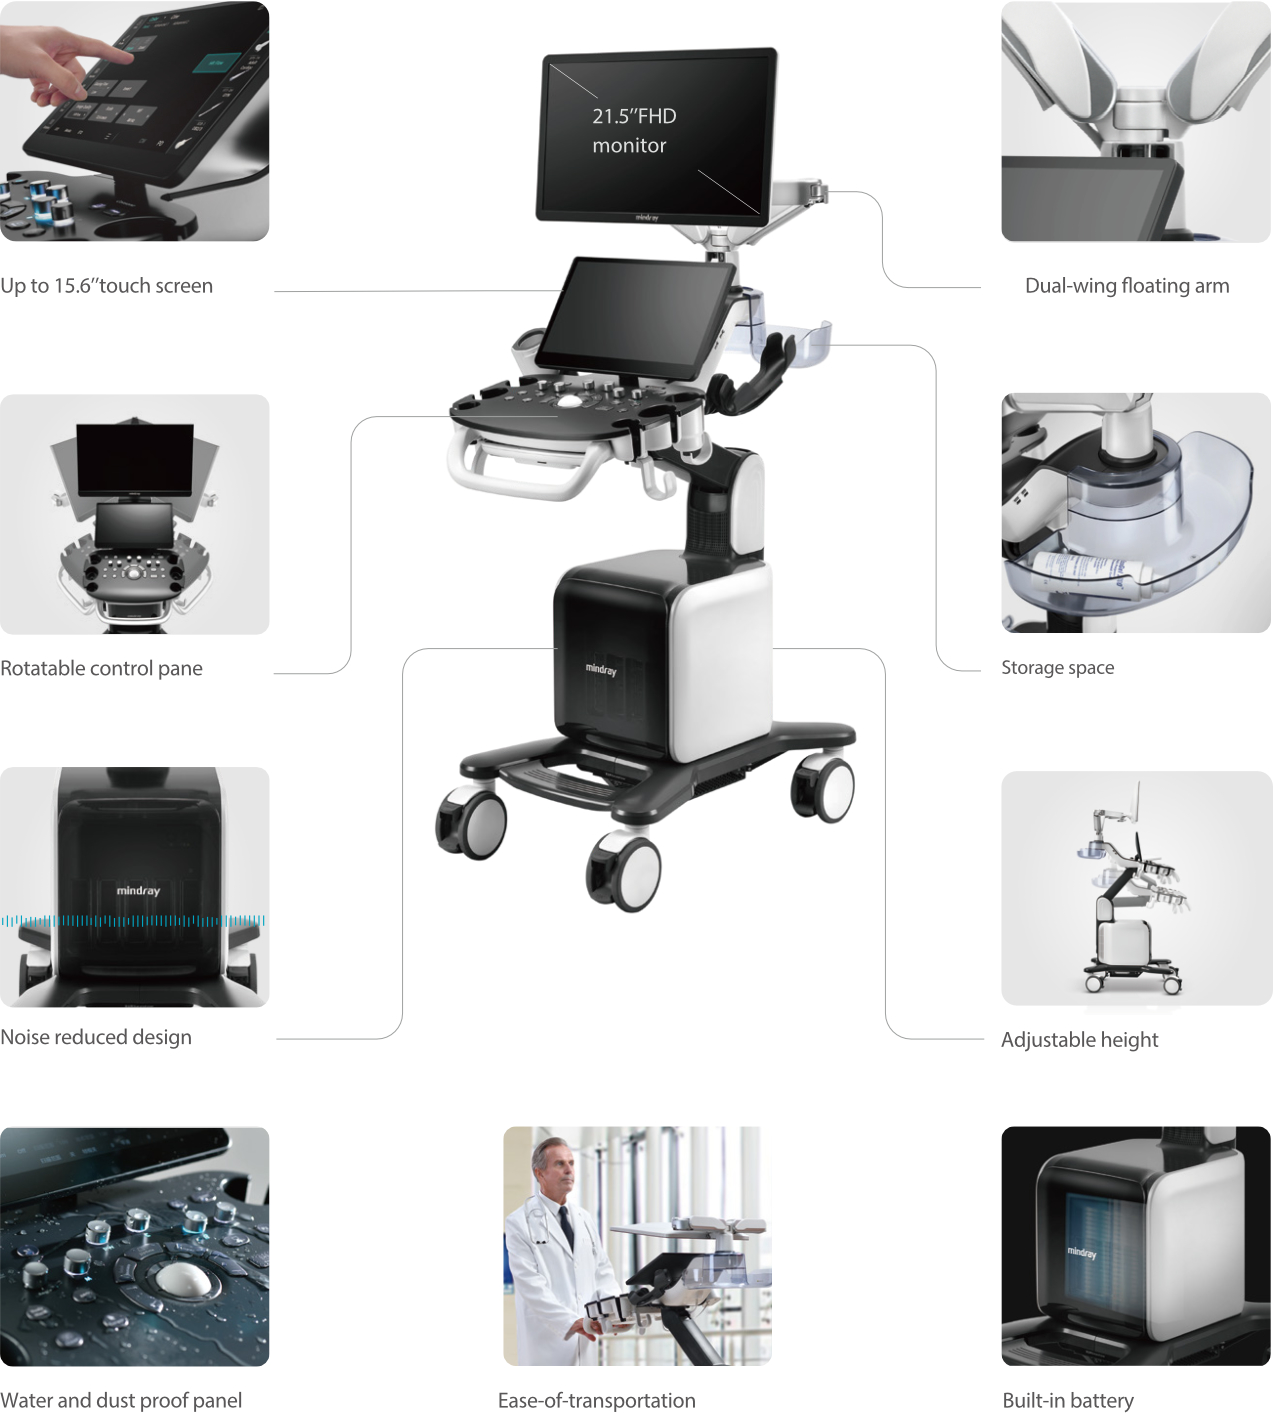

De Consona biedt nieuwe en concrete oplossingen die effici?nt helpen bij het stellen van een vlotte diagnose voor veel verschillende soorten pati?nten.

Ongeacht of u werkzaam bent in een ziekenhuis of kliniek, of uw vaardigheden aanscherpt op het gebied van algemene beeldvormingstoepassingen, vrouwengeneeskunde of cardiovasculaire specialismen, in deze serie vindt u zeer krachtige hulpmiddelen waarmee u aan kop kunt blijven.